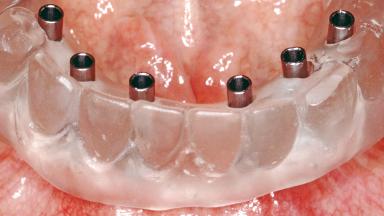

Conventional Loading of Six Implants in the Mandible and Final Restoration with a Full-Arch Metal-Ceramic FDP

# of Implants 6

Type of Implants One-Piece

Attachment One-Piece

Prosthesis Type FDP

Defining Characteristics Fully edentulous lower jaw to be rehabilitated with an implant-borne fixed dental prosthesis

Retention Screw-retained, with 4 or more splinted implants Screw-retained, with 4 or more splinted implants